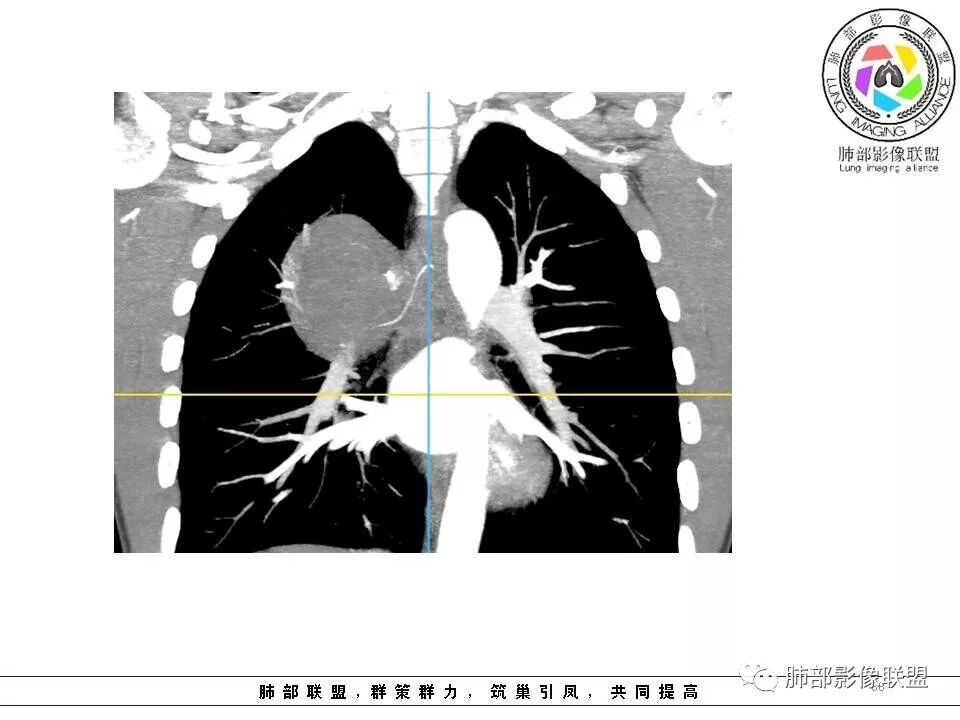

右肺占位,跨越上叶后段、下叶背,边缘光滑,瘤肺界面清,见肺压缩缘(线样不张`强化),见胸膜尾征,胸膜下脂肪未见明显增厚,肋骨丶脊柱未见侵袭及受压,渐进性丶地图样强化,冠状位似见体循环供血

诊断:SFT(来源壁层胸膜?一般小于20%)

边缘光滑,宽基底与胸壁相连,跨叶裂,叶裂稍前推,血管、支气管前移。

浅分叶

外上侧少量胸水

肋间动脉供血,强化尚均匀,逐步强化